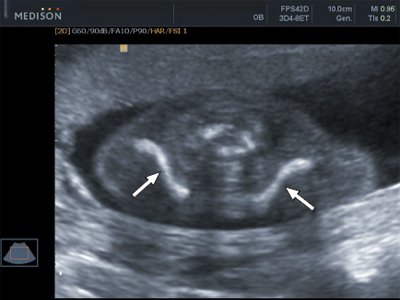

При визуализации ключиц плода было установлено, что их типичная вытянутая S-образная форма идентифицируется уже с начала II триместра и практически не изменяется на протяжении второй половины беременности (рис. 3, 4). При невозможности одновременной визуализации обеих ключиц осуществляли их раздельную идентификацию (рис. 5).

Рис. 3. Эхограмма ключиц (стрелки) плода в 16 недель беременности. Длина ключиц составляет 15 мм.